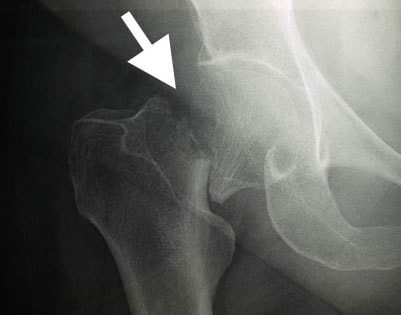

hip fracture

Most hip fractures are visible on an X-ray.

Image courtesy of Stuart J. Fischer, MD, FAAOS